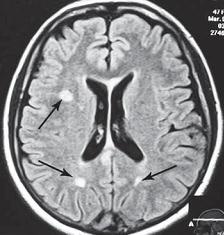

МРТ № 31 ![]() Он взял отпуск и поехал в Москву в довольно известную частную клинику. Прошёл курс лечения, который включал в себя «стандартный набор»: — мануальную терапию, с целью уменьшения (устранения) болевого синдрома, путём восстановления соотношений суставных поверхностей дугоотростчатых суставов в сегментах CV-CVI и CVI-CVII (устранение сублюксации); — массаж шейного отдела позвоночника (для расслабления мышц, улучшения кровообращения); — физиотерапию — магнитотерапию, инфракрасный лазер на воротниковую зону, с целью уменьшения воспалительных процессов и отёчности в поражённых тканях; — медикаментозную терапию — стандартный набор нестероидных препаратов, витамины и анальгетики; — физические упражнения на тренажёрах и лечебная физкультура для укрепления мышечного корсета позвоночника и выработки правильной осанки, придание связочно-мышечному аппарату необходимой гибкости с целью увеличения объёма движений в позвоночнике. После лечения действительно почувствовал себя лучше, работоспособность была восстановлена. Но, чтобы не утратить достигнутый результат лечения, следуя рекомендациям, полученным в московской клинике, он продолжил заниматься на тренажёрах. Даже приобрёл несколько универсальных (многофункциональных) тренажёров. Один установил дома, другой — на работе. Жизнь вошла в привычное русло. Боли в шее периодически возникали, но проходили после занятий на тренажёре. К медикаментам прибегал в редких случаях. Так продолжалось практически год, пока не появилась боль в левой руке и онемение IV и V пальцев. Занятия на тренажёре только усиливали боли, а лекарства практически не действовали. В связи с чем он был вынужден опять обратиться в ту же клинику. После лечения (практически по той же схеме) боли уменьшились, но полностью не прошли, онемение усилилось. Через некоторое время появилась субфебрильная температура (37–37,2 °C), общая слабость, частые головные боли, головокружения. По жалобам и ощущениям с его слов: «На голову надели будто тесную шапку и она сдавливает. А в голове туманность какая-то, мысли путаются, на чём-то сосредоточиться практически невозможно. Порой забываю, что минуту назад делал. Такое ощущение, что в голове полно посторонних мыслей: только от одних отделаюсь, как появляются другие» и так далее. Естественно, он вынужден был опять обратиться в медицинское учреждение, где ему повторно сделали МРТ (№ 32). ![]() После обследования у него было обнаружено: — абсолютный стеноз спинномозгового канала шейного отдела позвоночника с полным блоком ликворных путей и сдавлением дурального мешка спинного мозга на уровне сегментов CV-CVI и CVI-CVII; — в сегменте CV-CVI — значительный спондилёз, гипертрофия задней продольной связки, и практически компенсированная спондилёзом грыжа межпозвонкового диска; — в сегменте CVI-CVII — довольно активная грыжа межпозвонкового диска; — на уровне поражённых сегментов выраженный эпидурит. После данного обследования, когда врачи увидели грыжи межпозвонковых дисков, да и то, что происходило у пациента в шейном отделе позвоночника, они стали категорически настаивать на немедленной операции. Однако перспектива стать инвалидом на всю оставшуюся жизнь явно не прослеживалась в планах пациента. Когда прозвучали два слова — «грыжи» и «операция», этот человек, естественно, тут же вспомнил и про меня, и про нашу давнишнюю с ним дружбу. Однако меня не удовлетворили результаты его обследования. Если бы дело было только в грыжах, это полбеды. Меня смущало наличие других симптомов, которые косвенно свидетельствовали о возможном поражении ЦНС. Поэтому я послал его на дополнительные обследования МРТ головного мозга (№ 33), тесты (ИФА (иммуноферментный анализ), ПЦР (Полимеразная Цепная Реакция на инфекции), которые дали положительный результат на герпесвирусы: Epstein-Barr virus (EBV) (вирус Эпштейна-Барр) и Cytomegalovirus (CMV) (вирус Цитомегаловирус). МРТ № 33

МРТ № 33 На МРТ отчётливо видны множественные очаги демиелинизации, вследствие развития нейроинфекции Этот случай очередной раз указывает на то, как даже гениальный мозг может пострадать от банальной глупости человеческой. Есть такие замечательные слова древнекитайского философа Лао-Цзюнь (Лао-Цзы) в «Рассуждениях о ста заболеваниях»: «Человек мудрости… избавляется от беды, когда она ещё не появилась. Ведь катастрофа рождается из мелочей, а болезнь возникает из тончайших отклонений». Грыжа Шморля Некоторых моих пациентов интересует вопрос, что такое грыжа Шморля, которая у них была обнаружена в результате обследования. Грыжа Шморля (хрящевой узелок Шморля, узелок Шморля) — это медицинский термин, который означает грыжевидное выпячивание, внедрение хрящевой ткани из межпозвонкового диска в губчатую кость тела позвонка. Названа она так в честь выдающегося немецкого патологоанатома, учёного, профессора Кристиана Шморля (Schmorl Ghristian Georg; 1861–1932), который первым описал данную патологию в рамках научного понимания начала XX века. За последние годы жизни учёный написал ценные работы по патологической анатомии позвоночника. В них профессор Шморль поделился рядом своих открытий, касающихся межпозвонковых дисков. В том числе там было описано состояние межпозвонкового сегмента, при котором межпозвонковым диском была продавлена замыкательная (гиалиновая) пластинка, отделяющая губчатую кость тела позвонка от межпозвонкового диска. Очаги данной патологии могут появиться у человека ещё в детском, подростковом возрасте. Как правило, они не имеют клинических проявлений, поэтому человек не чувствует каких-либо болевых ощущений. Но и здесь бывают свои исключения. На МРТ № 34 наблюдаются грыжи Шморля (обратите внимание на локализацию пульпозных ядер межпозвонковых дисков), при которых пациент не испытывает болевых ощущений. Данные грыжи опасений не вызывают. А вот на снимке МРТ № 35 наблюдаются грыжи Шморля с глубоким проникновением межпозвонковых дисков в тела позвонков со значительным разрушением последних. Это уже опасно. Тем более что у пациента остеопороз (дистрофия костной ткани, в результате которой кости становятся хрупкими и ломкими), что означает неизбежное прогрессирование данной патологии. А это, в свою очередь, увеличивает риск возникновения патологических переломов тел позвонков в местах развития грыж Шморля. Но не всё так уж и печально для данного пациента: если подлечить остеопороз, да в последующем бережно относиться к своему здоровью, то есть ещё шанс избежать серьёзных осложнений этого заболевания позвоночника. |